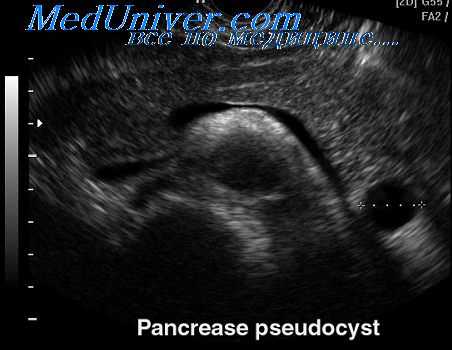

Высокоинформативны инструментальные методы визуализации кисты. УЗИ поджелудочной железы позволяет оценить размеры образования, а также косвенные признаки осложнений: в случае нагноения определяется неравномерность эхосигнала на фоне полости, при малигнизации – неоднородность контуров. Компьютерная томография и магнитно-резонансная томография (МРТ поджелудочной железы) дают более детальную информацию о размерах, расположении кисты, наличии ее связи с протоками. В качестве вспомогательного метода может применяться сцинтиграфия, при которой киста определяется как «холодная зона» на фоне общей паренхимы органа.

При проведении рентгенографии органов брюшной полости возможно обнаружение тени псевдокисты, а также смещения двенадцатиперстной кишки или желудка. Более информативна ультразвуковая диагностика. УЗИ поджелудочной железы позволяет визуализировать ложную кисту, оценить ее локализацию и размеры, в некоторой степени – связь с протоковой системой, а также наличие или отсутствие осложнений (нагноения, кровоизлияния в полость). В случае сдавления холедоха выявляется расширение желчных протоков, при портальной гипертензии – селезеночной и воротной вен. При малигнизации псевдокисты визуализируются неровные контуры ее стенки.

КТ органов брюшной полости. Псевдокиста поджелудочной железы у пациента после приступа острого панкреатита